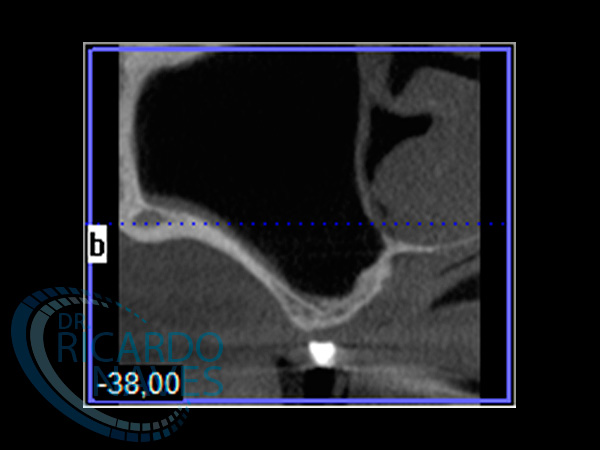

Obsérvese la gran atrofia a nivel de senos maxilares en donde seria imposible instalar implantes sin instalar injertos.

Tomografía post exodoncias con marcadores radio opacos en prótesis de trabajo.